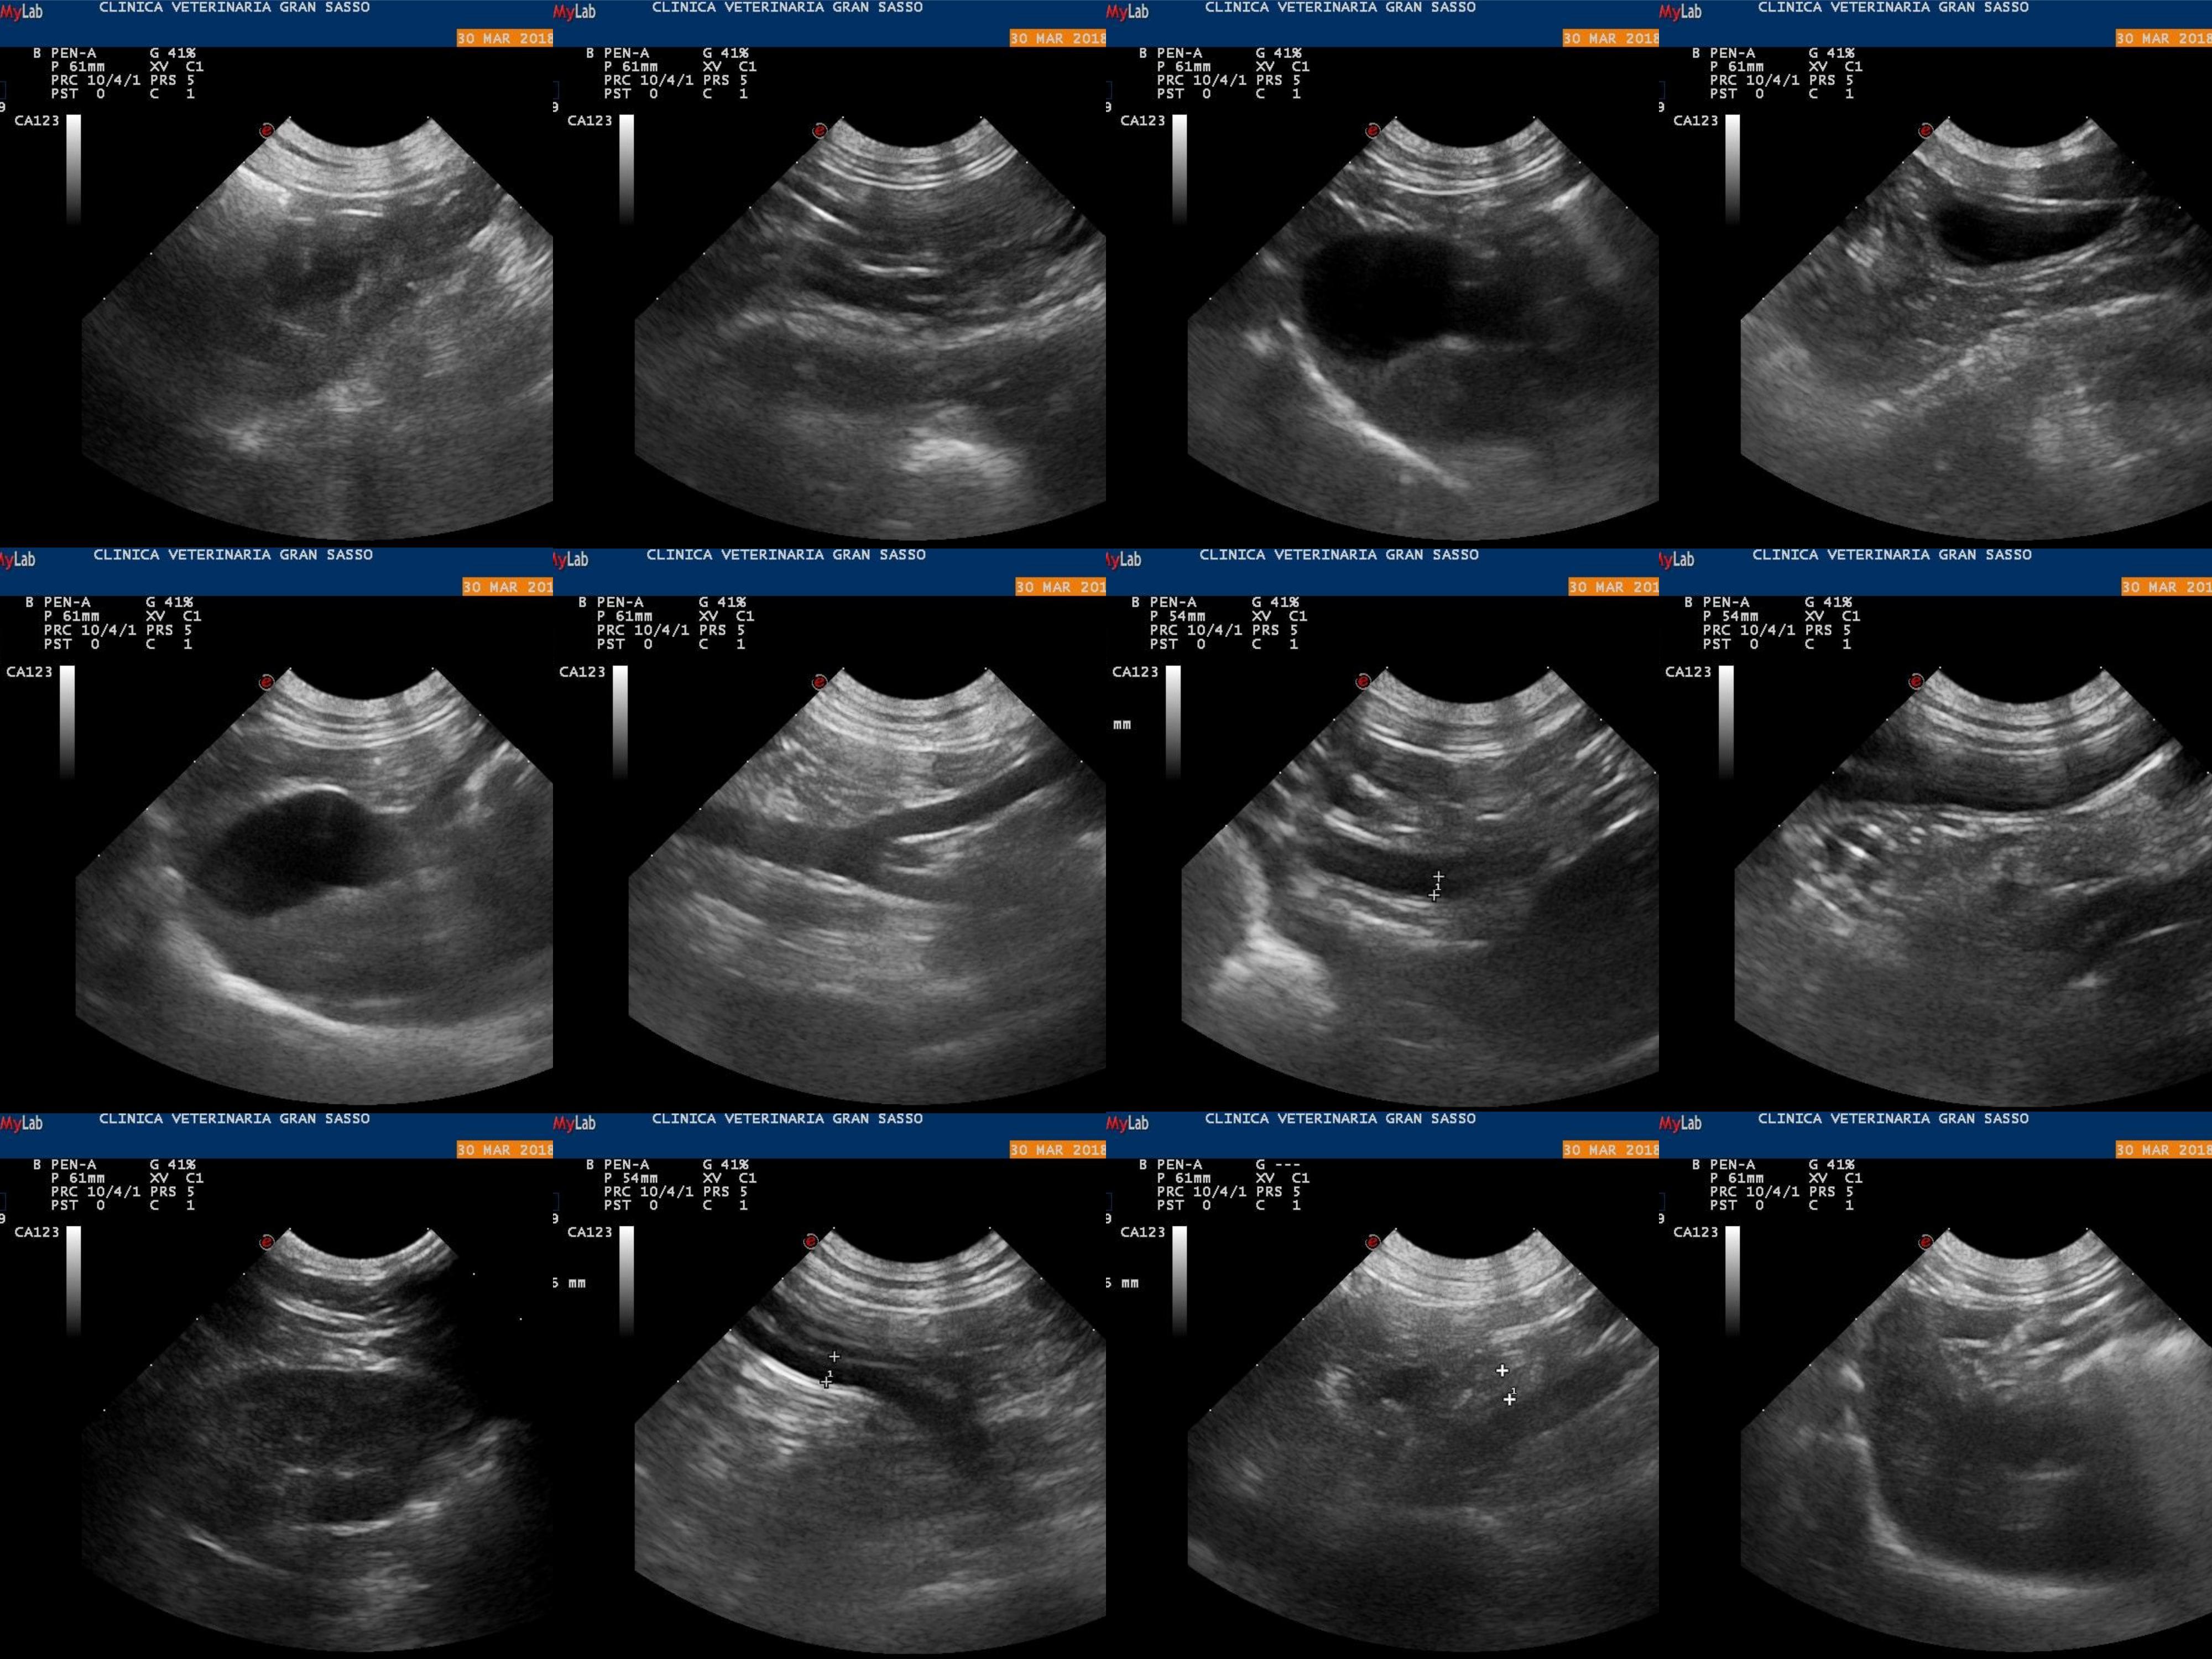

Beatrice display hypomotility, pain, temporary shaking after walking, lip licking and yellow feces. Doctors are unsure if it is enteritis, pancreatitis, or disk herniation. Thank you in advance for your help, Luca

Those are all possible causes. In cases like this, we usually need to treat symptomatically. The normal treatments for pancreatitis would also treat enteritis. Beatrice would need an MRI to determine if she has a herniated disk, but she could be treated with pain medication (which she also needs for possible pancreatitis) in the mean time. I can't tell you which issue is the cause (or they are all a factor) from these images, but I share your vet's concern about all of them.